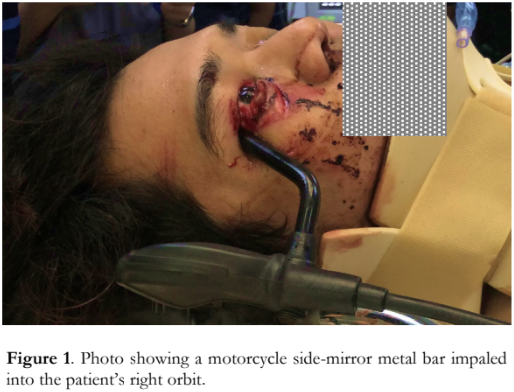

A 26-year-old Filipino male presented to the emergency room after sustaining a transorbital penetrating intracranial injury after being struck by an oncoming motorcycle. Past medical history of the patient was unremarkable. On physical examination, he had a Glasgow Coma Scale score of 12 (E4V3M5) and his vital signs were stable. The motorcycle side-mirror metal bar was impaled into his right orbit at the lateral canthus (Figure 1). Ophthalmic examination revealed upper eyelid avulsion, detachment of the lower eyelid from the lateral canthus, and upper and lower canalicular system transection. The pupil of the right eye was round, dilated and non-reactive to light. The visual acuity could not be properly assessed due to poor verbal response of the patient. The examination of the left eye revealed no abnormalities.